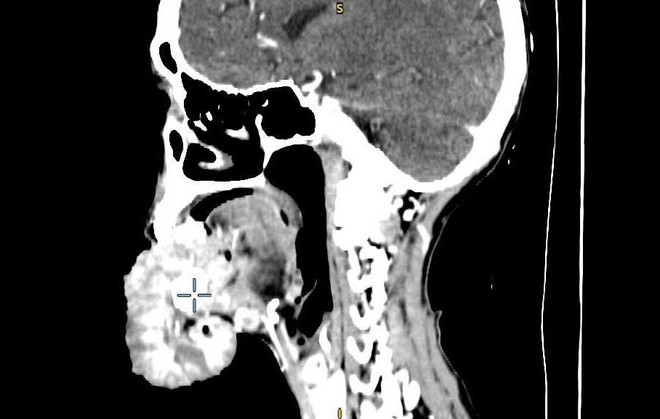

Phẫu thuật cắt bỏ khối u ung thư đường kính 20cm ở môi một phụ nữ ảnh 1Phim chụp khối u của bệnh nhân. (Ảnh: PV/Vietnam+)

Kết quả phim chụp cắt lớp vi tính cho thấy khối u vùng môi dưới kích thước lớn 15x20cm, xâm lấn xương hàm dưới, sàn miệng, lưỡi, di căn nhiều hạch cổ hai bên kích thước 2-3 cm. Bác sỹ chỉ định cho bệnh nhân Y. nhập viện với chẩn đoán ung thư môi dưới T4N2M0.